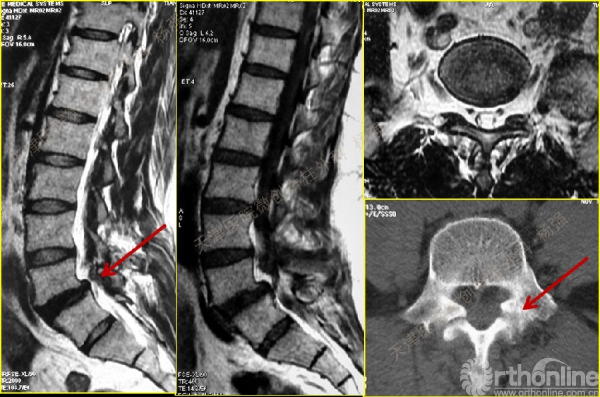

CT、MRI示:腰5椎体前滑脱,腰5/骶1水平间盘突出,腰5双侧椎弓峡部裂